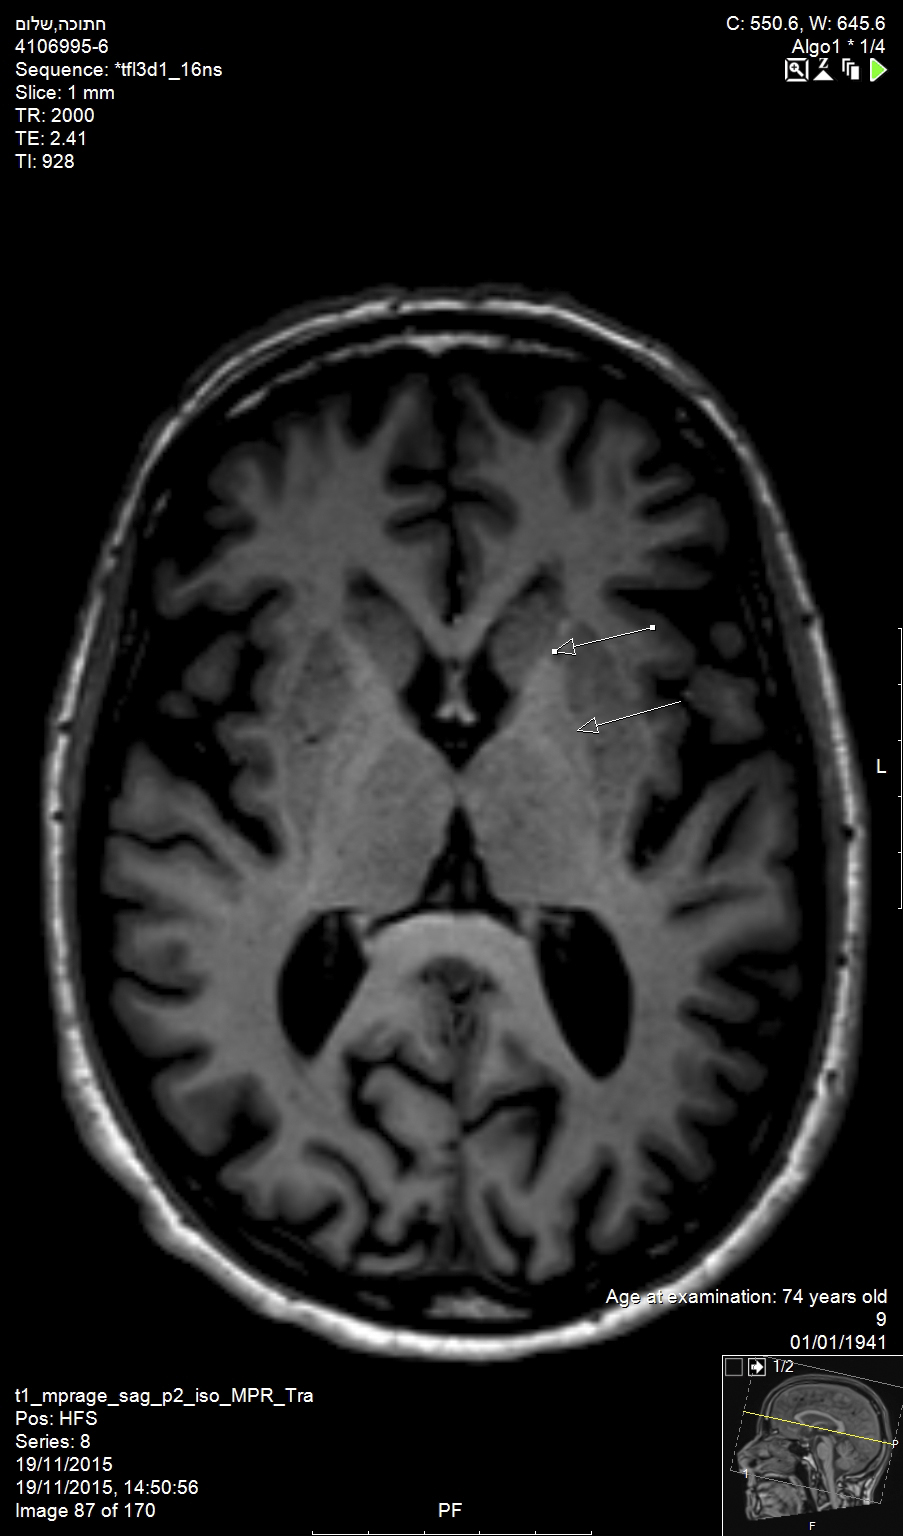

As a follow-up, the patient was guided to a strict oral hygiene and periodontal dental hygienist treatment regimen (Figure 5).

Fig 5. The completed treatments at 6-month follow-up.

Figure 5